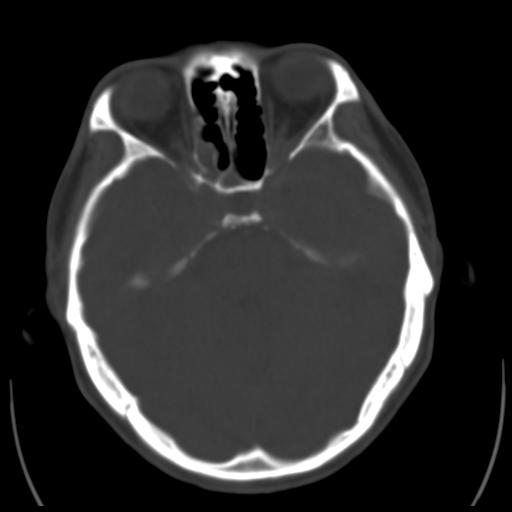

35m 鼻子时不时流血,头及右侧面部痛,颈部淋巴结未见明显大

骨窗

这个东西大家仔细看看呀

蝶窦,后组筛窦及鼻咽部团块状软组织影,骨壁破坏,病变较广泛。考虑恶性肉芽肿。建议活检。

颅底骨质明显破坏 支持鼻咽癌 但病灶的边缘毛糙 不能除外炎性

考虑中线肉芽肿(鼻硬结病),次之tb或真菌感染性肉芽肿,病变形态不像肿瘤,建议增强及活检。

蝶窦,后组筛窦及鼻咽部团块状软组织影,骨壁破坏,病变较广泛。考虑炎性肉芽肿性病变可能。建议活检。

颅底骨质不是那种溶骨性的破坏吗?